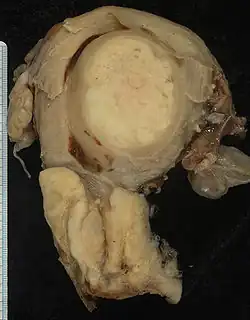

Histologic subtypes of invasive cervical carcinoma include:[71][72]

- Squamous cell carcinoma (about 80–85%[73][74])

- adenocarcinoma (about 15% of cervical cancers in the UK[68])

- Adenosquamous carcinoma

- Small cell carcinoma

- Neuroendocrine tumour

- Glassy cell carcinoma

- Villoglandular adenocarcinoma

Though squamous cell carcinoma is the cervical cancer with the highest incidence, the incidence of adenocarcinoma of the cervix has been increasing in recent decades.[5] Endocervical adenocarcinoma represents 20–25% of the histological types of cervical carcinoma. Gastric-type mucinous adenocarcinoma of the cervix is a rare type of cancer with aggressive behavior. This type of malignancy is not related to high-risk human papillomavirus (HPV).[78] Noncarcinoma malignancies, which can rarely occur in the cervix, include melanoma and lymphoma. The International Federation of Gynecology and Obstetrics (FIGO) stage does not incorporate lymph node involvement in contrast to the TNM staging for most other cancers. For cases treated surgically, information obtained from the pathologist can be used in assigning a separate pathologic stage, but is not to replace the original clinical stage.